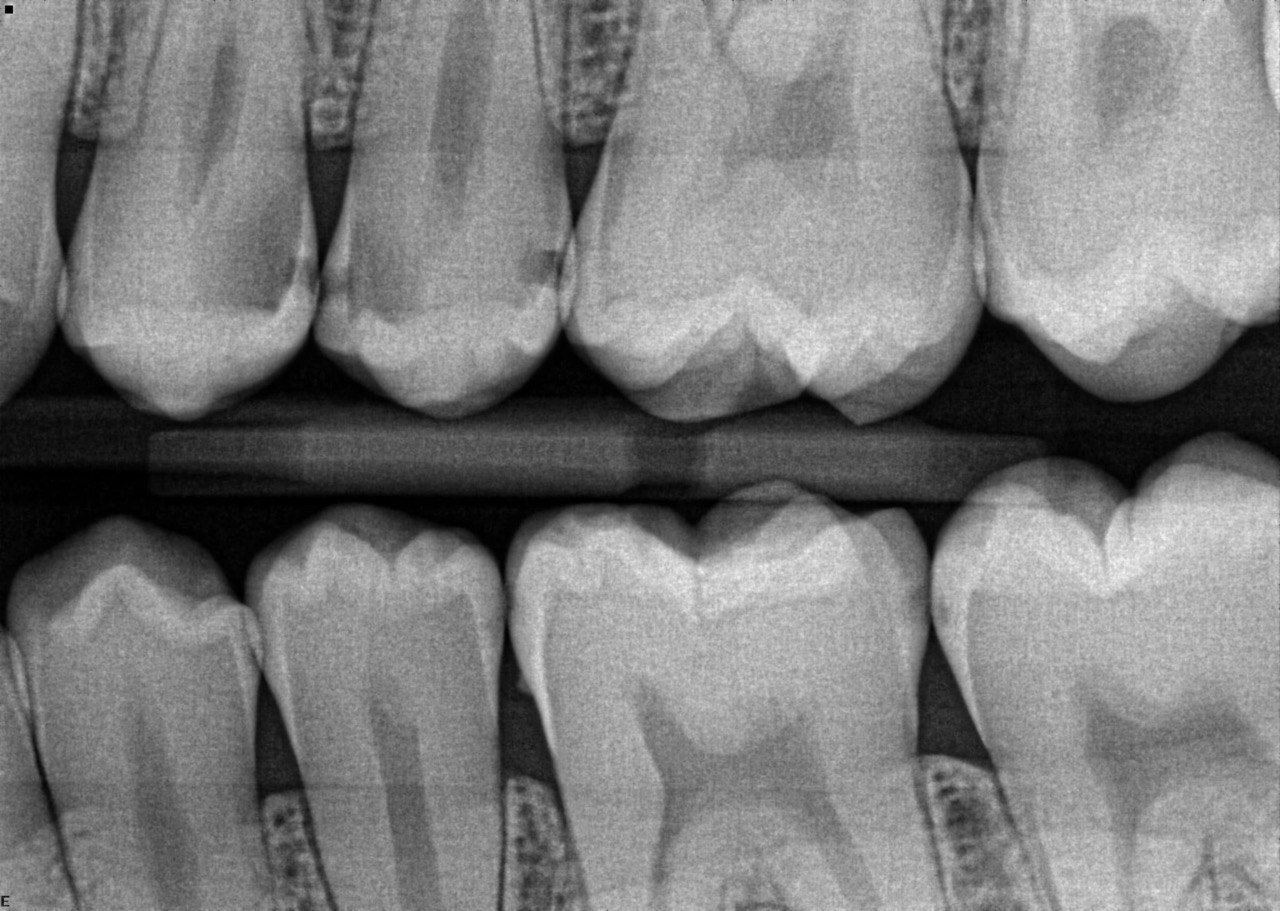

4. What surface require restoration?